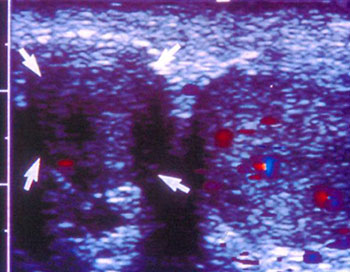

Εικόνα 8. Η ενδοωοθηκική

ροή αίματος την 6η, ή το πολύ την 7η ημέρα θεραπείας, είναι πλέον επαρκής, ώστε

να είναι δυνατή η καταγραφή της με τη μέθοδο Doppler, ενώ η απουσία της είναι

πρώιμος δείκτης πλημμελούς ανταπόκρισης. Αντίθετα, όπως εμφανίζεται στην εικόνα,

η πρώιμη εντόπιση των ενδοωοθηκικών νεόπλαστων αγγείων (πριν την 5η ημέρα θεραπείας),

με ιδιαίτερα χαμηλές αντιστάσεις (PI: 0,59 και RI:0,39), αποτελεί πρώιμο δείκτη

επικείμενης ωοθηκικής υπερδιέγερσης και ένδειξη για αναπροσαρμογή της θεραπείας.

Η ανάλυση Doppler των ενδοωοθηκικών αγγείων, κυρίως του στρώματος, μπορεί να

χρησιμεύσει για την πρόγνωση της ικανοποιητικής ή μη ανταπόκρισης των ωοθηκών

στη διέγερση με γοναδοτροπίνες. Συγκεκριμένα, σύμφωνα με δικές μας παρατηρήσεις,

σε γυναίκες με ικανοποιητική ανταπόκριση, η ενδοωοθηκική ροή αίματος την 6η

ή το πολύ 7η ημέρα θεραπείας, είναι πλέον επαρκής, ώστε να είναι δυνατή η καταγραφή

της με τη μέθοδο Doppler. Αντίθετα, η αδυναμία καταγραφής κυμάτων ροής αίματος

μέχρι και την 7η ημέρα θεραπείας, κατά κανόνα συνοδεύεται από φτωχή τελική ανταπόκριση

και αποτελεί ένδειξη για αύξηση της δοσολογίας. Η εντόπιση εξάλλου με τη μέθοδο

Doppler, νεόπλαστων ενδοωοθηκικών αγγείων, με ιδιαίτερα χαμηλές αντιστάσεις

πριν από την 5η ημέρα θεραπείας, αποτελεί πρώιμο δείκτη επικείμενης ωοθηκικής

υπερδιέγερσης και ένδειξη για αναπροσαρμογή της θεραπείας (εικόνες 8, 9).